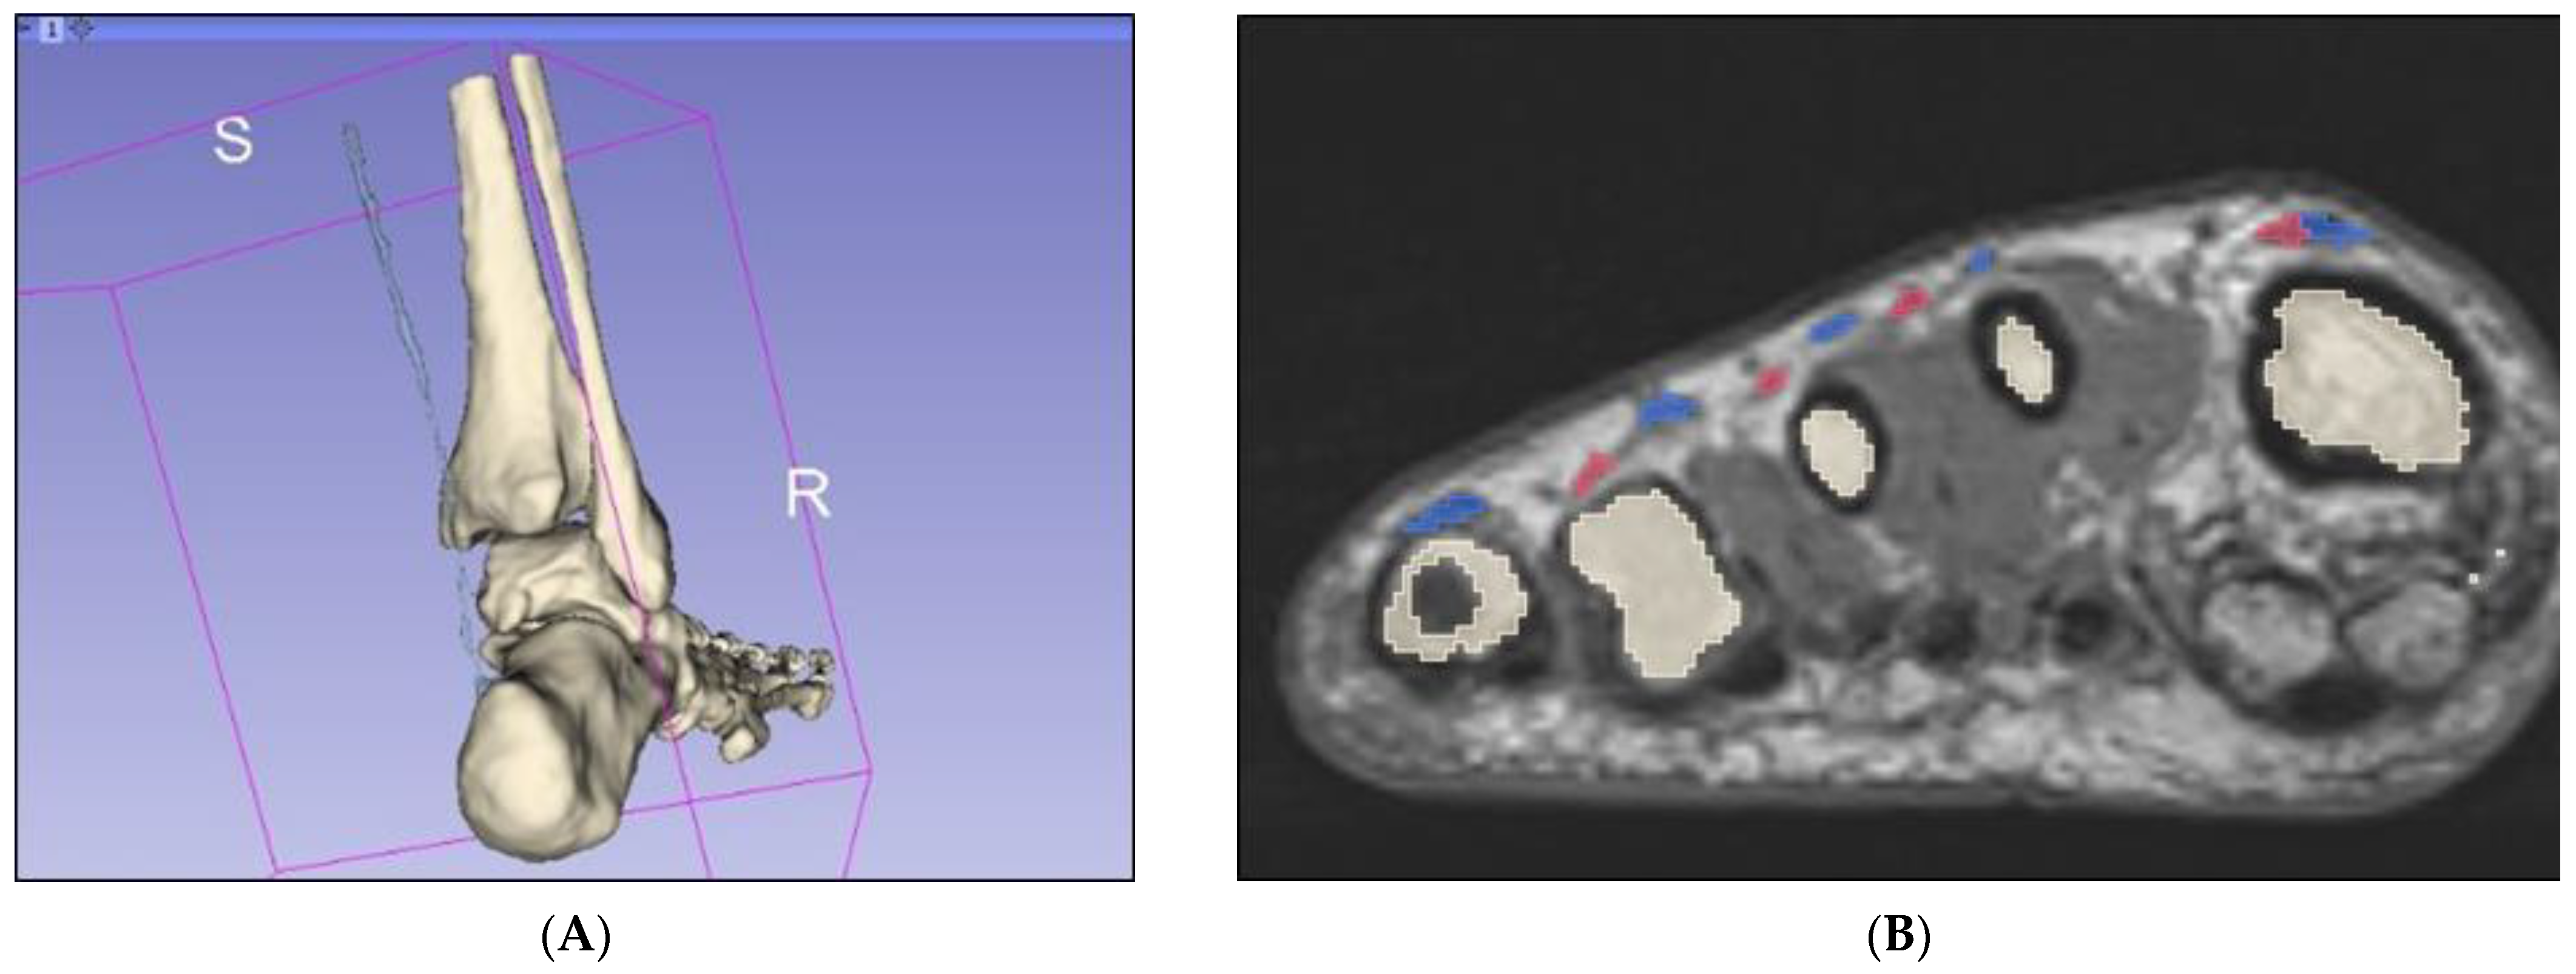

2.2. Segmentation of Bony Anatomy

2.4. Creation of Mixed Reality